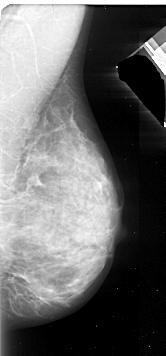

A_1092_1.RIGHT_MLO

RIGHT_MLO LINES 5326 PIXELS_PER_LINE 2476 BITS_PER_PIXEL 16 RESOLUTION 42 NON_OVERLAY